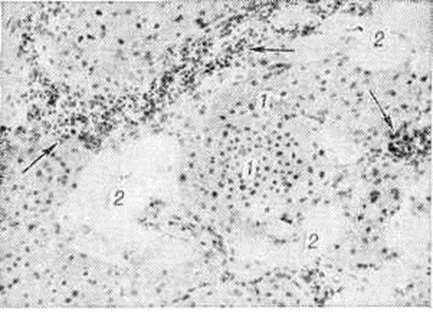

Микроскопически опухоль состоит из комплексов крупных, величиной от 40 до 100 микрометров в диаметре, овальных, полигональных, иногда вытянутой формы клеток (рисунок), в цитоплазме которых содержатся крупные, равномерно расположенные зерна, дающие слабоположительную реакцию на липиды и ШИК-реакцию; иногда в цитоплазме клеток Миобластома зернисто-клеточная обнаруживаются капельки жира. Ядра опухолевых клеток округлой формы, расположены центрально; фигуры митоза обычно отсутствуют, однако часто бывают видны ядра с перетяжкой или делящиеся амитотическим путём. Строма нежноволокнистая, бедная сосудами.

Рис

Микропрепарат зернисто-клеточной миобластомы: видны комплексы опухолевых клеток (1), инфильтрирующих жировую ткань (2), в строме опухоли отмечается очаговая инфильтрация лимфоидными клетками (указана стрелками); окраска гематоксилин-эозином; × 100.